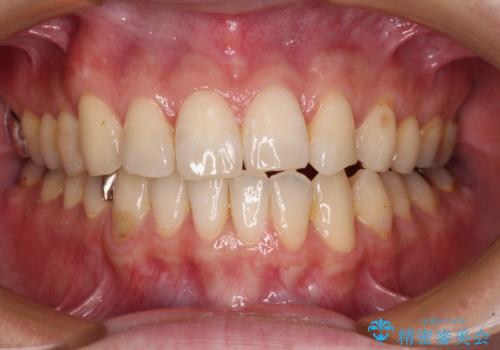

- デコボコした前歯をセラミックできれいに揃えたいとのことで来院された患者様です。

歯を削って整えることは簡単ですが、健全な歯を削って後悔してからでは遅いため、矯正治療を提案しました。

はじめは矯正治療の期間が長いことに悩んでいらっしゃいましたが、ある程度整えば満足するだろうとのことで、インビザラインにて矯正治療を行うこととしました。

左上の犬歯が欠損しているため、正中の位置や奥歯の咬み合わせが理想的にならない点を了承していただきました。

インビザライン矯正は、1日22時間を目安に装着する必要がありますが、しっかりと装着してくださったので、順調に治療を進めることができました。